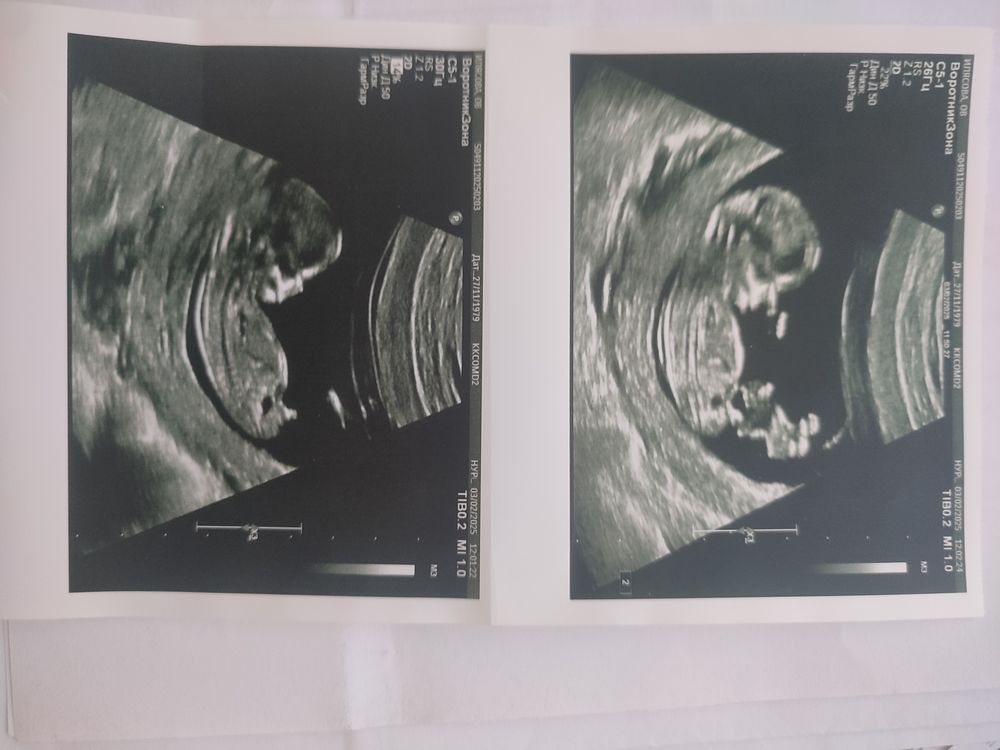

Про половой бугорок...

Мальчик

Оксана, у мальчик бугорок к верху торчит. У девочек прямо. Я с последним так же на 1 скрининге увидела. Оказался мальчик.

Это точно мальчик 🐣

Как бы видно очень даже отчетливо,не скрыть ничем 😂

Да, похож на мальчика)

Да мальчик